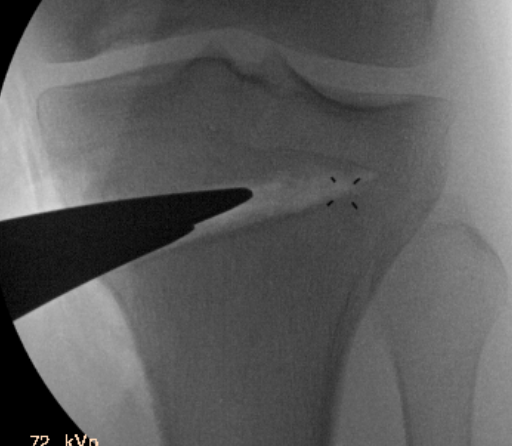

Guide pins for osteotomy and checking posterior slope

Osteotomy to within 1cm of the lateral cortex

Consider lateral hinge 2 mm K wire

- 10 mm from lateral cortex

- distal to proximal